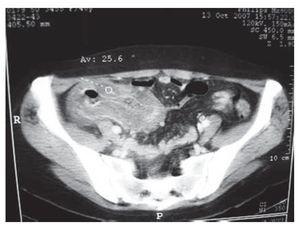

Ocho pacientes presentaron ECN (6.8%). La mitad de los casos fueron del sexo masculino con edad promedio de 25.8 años (rango 16 a 51 años). Las características generales se muestran en la Tabla 2. Se realizó radiografía simple del abdomen en 6 de los 8 pacientes que mostró distensión de asas intestinales en 2 pacientes y datos inespecíficos en el resto. Se realizó TC abdómino-pélvica a 7 de los 8 pacientes con presencia de engrosamiento de la pared en 6 pacientes y líquido pericólico en 2 (Figuras 1 y 2). El ultrasonido abdominal no se utilizó como estudio diagnóstico en esta serie de casos.

Figura 2. Tomografía axial computarizada de abdomen mostrando ciego y colon ascendente con engrosamiento importante de la pared y disminución de la luz